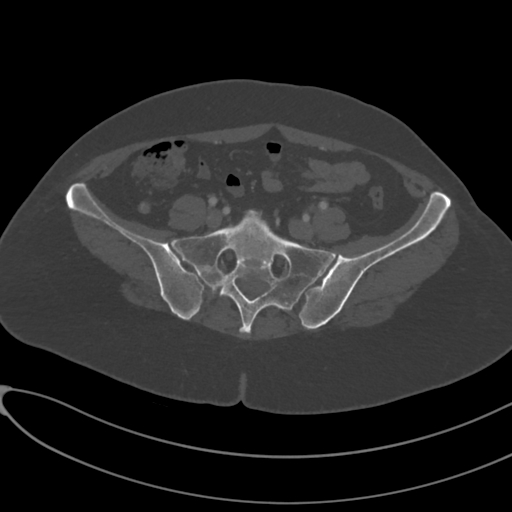

For the BM segmentation task, we compared the predicted masks generated by our approach with those from three competitive methods (Figure 5), which had proven to be the top performers, as shown in Table 3. These competitors include MISSFormer Huang et al. (2022), UCTransNet Wang et al. (2022a), and EDAUnet++ Afnouch et al. (2023). In the first two examples, we examined cases where Bone Metastasis had infected all bone regions within the slice. A closer inspection of the predicted masks revealed that most approaches were successful in highlighting the infected regions. However, it was evident that MISSFormer and EDAUnet++ struggled to capture segmentation details accurately. In contrast, our approach and UCTransNet excelled in matching the details present in the ground-truth masks. The remaining three examples represented slices where only a portion of the bone was infected by BM, which is a particularly challenging aspect of BM segmentation. In the third example, the comparison methods incorrectly segmented a part of the bone as a Bone Metastasis lesion. In contrast, our approach accurately matched the ground-truth mask in these scenarios. The last two examples demonstrated our approach’s ability to capture intricate lesion details effectively, showcasing the efficiency of our proposed compound encoder, which integrates Transformer and CNN features. In summary, the visualizations and comparisons reaffirm the effectiveness of our approach in BM segmentation, particularly in challenging cases, and highlight its ability to capture intricate lesion details efficiently.

Slice Bone Mask MISSFormer UCTransNet EDAUnet+ D-TrAttUnet GT

Figure 5: Visual Comparison of Bone Metastasis Segmentation Models Trained with Different Architectures.